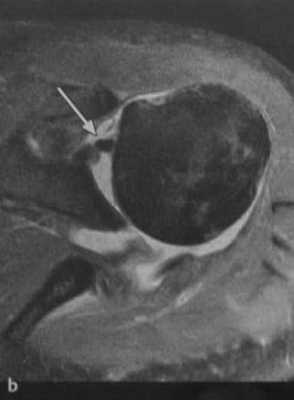

(b) Аксиальная МРТ. Смещение сухожилия двуглавой мышцы и изображение «пустой борозды» (стрелка).